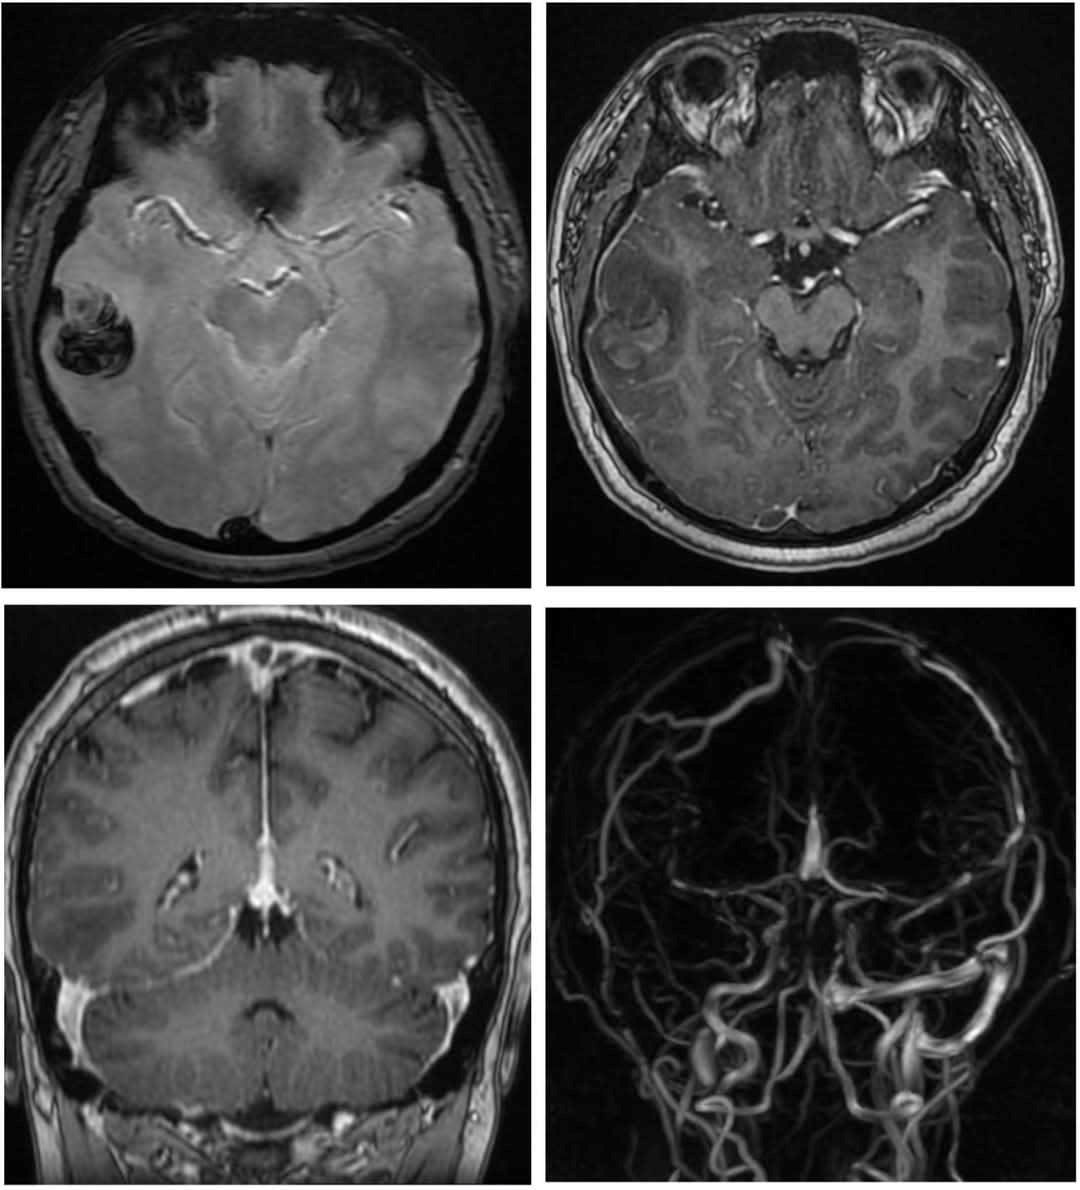

PGS.TS Nguyễn Huy Thắng -Trưởng khoa Bệnh lý mạch máu não, Bệnh viện Nhân dân 115 (TP.HCM), cảnh báo: hút shisha thường xuyên có thể trực tiếp gây huyết khối và đột quỵ. Trong tháng 3/2025, ông từng tiếp nhận một bệnh nhân 22 tuổi ở Cà Mau bị xuất huyết não nguy kịch, có tiền sử hút shisha dài ngày.

Cơ chế được giải thích như sau: Nicotine làm tăng đông máu. Khí CO làm giảm oxy, gây stress cho hệ tuần hoàn. Kim loại nặng như chì, cadmium cùng các hợp chất hữu cơ độc hại gây viêm và tổn thương nội mạc tĩnh mạch.

Tất cả tạo môi trường lý tưởng để huyết khối hình thành, làm tăng nguy cơ nhồi máu não và đột quỵ ngay cả ở người trẻ.